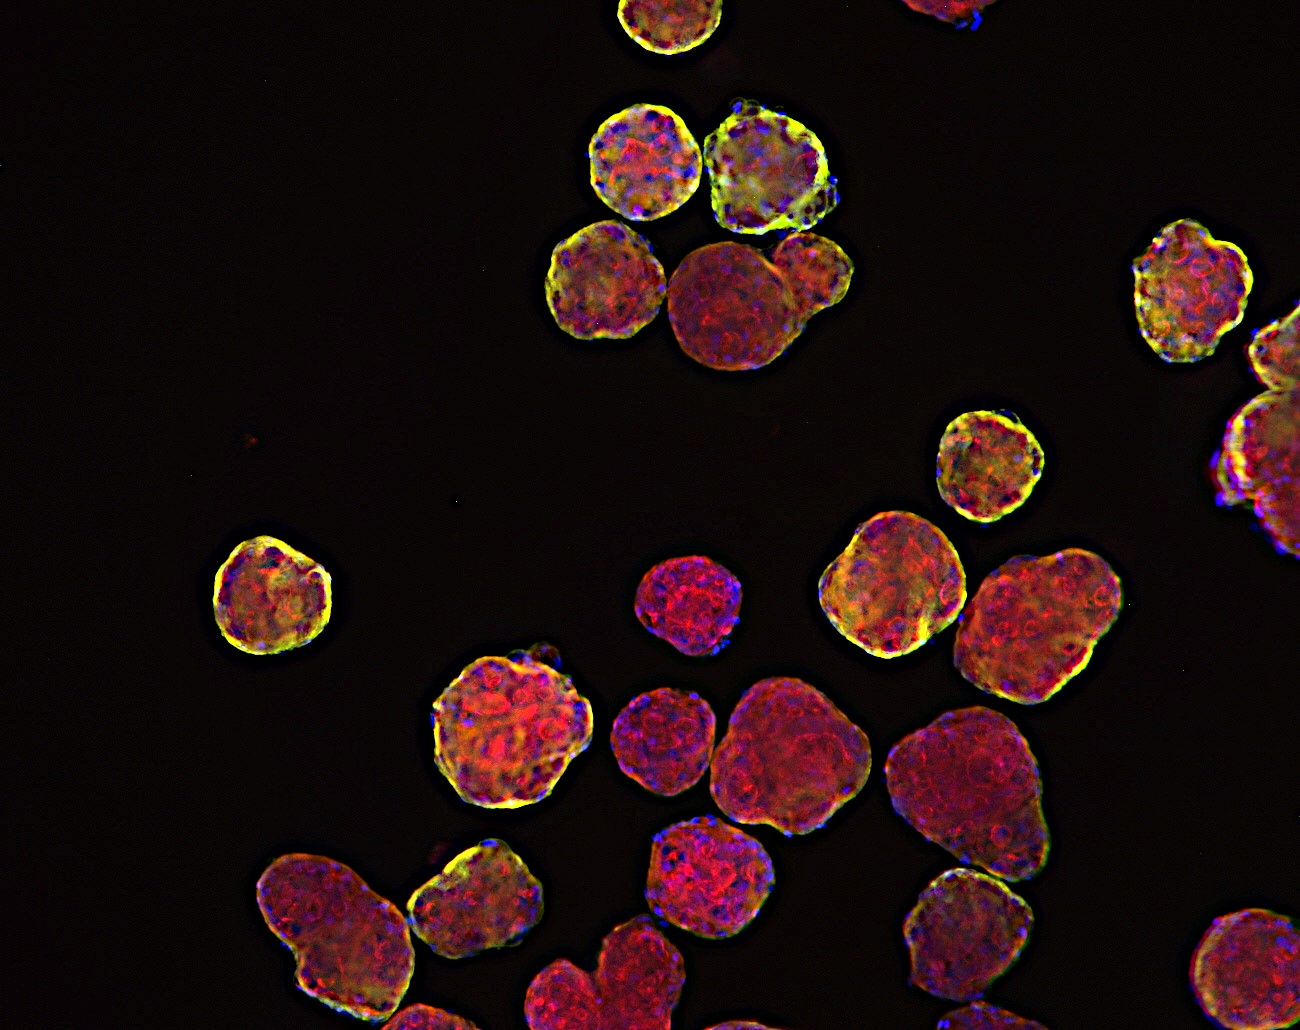

Visualisation of PDX organoid

Triple negative breast cancer derived xenograft organoid

Pancreatic ductal adenocarcinoma derived xenograft organoid

Colorectal cancer derived xenograft organoid